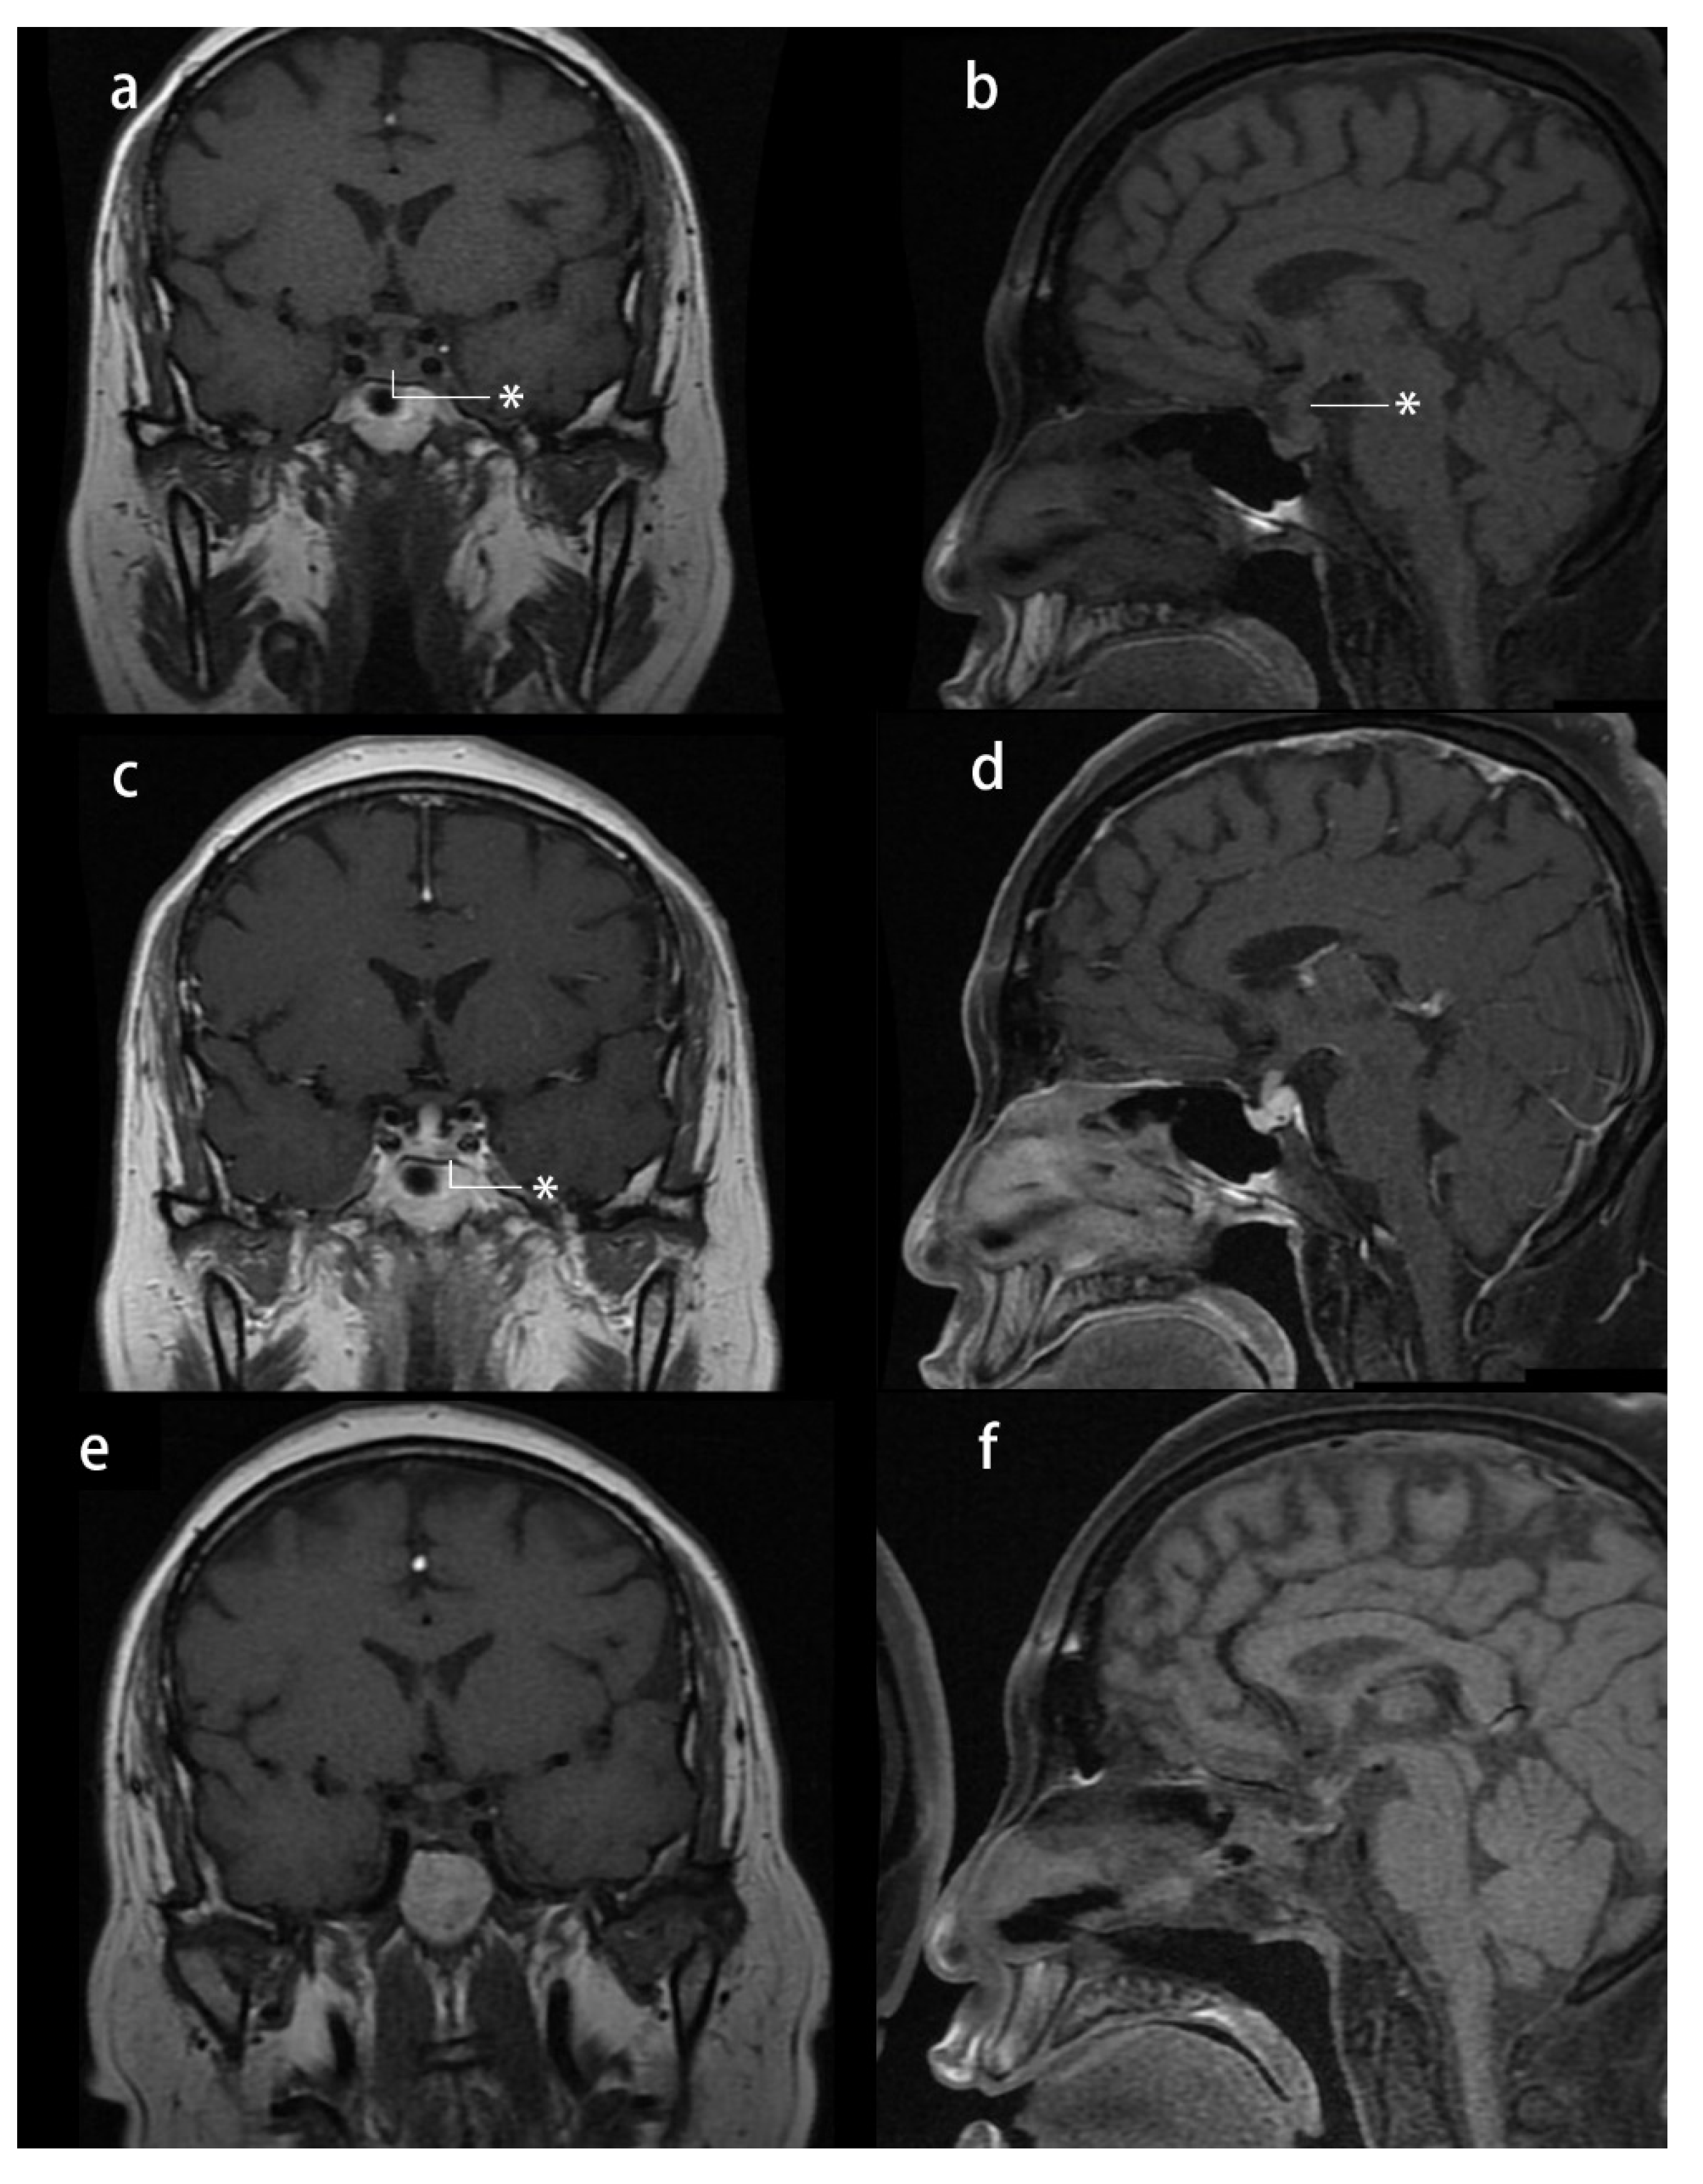

Her physical examination revealed moon face, central obesity, abdominal striae, and lower extremity edema. Her height was 164 cm, and her weight was 83 kg, with a body mass index (BMI) of 30.86 kg/m2. She had a history of hypertension, impaired glucose tolerance, and hyperlipidemia and had 5 months of menopause. Her blood pressure was approximately 130/80 mmHg when on a daily dose of 30 mg of nifedipine. Her midnight serum cortisol was 17.37 µg/dL, and her ACTH level was 55.7 pg/mL (reference range: 0–46 pg/mL), with 24 h urinary-free cortisol (24 h UFC) of 186.53 µg (reference range: 12.3–103.5 µg). An overnight 1 mg dexamethasone suppression test showed unsuppressed serum cortisol (3.09 µg/dL), whereas a high-dose dexamethasone suppression test showed suppressed serum cortisol (1.09 µg/dL). Dynamic pituitary MRI revealed a 9.7 × 4.0 mm lesion at the left side of the pituitary gland, with a thickened pituitary stalk (4.3 × 2.9 mm) and the loss of T1 signal hyperintensity in the posterior pituitary gland (Figure 1). She received a diagnosis of CD based on these data. Furthermore, central diabetes insipidus was diagnosed based on a water restriction test: Urine osmolarity was 105 mOsm/kgH2O, serum osmolarity was 323 mOsm/kgH2O, and serum sodium was 156 mmol/L at 8 h water restriction. Urine output dropped from 4370 mL/24 h to 1440 mL/24 h after treatment with 0.1 mg desmopressin. However, the cause of diabetes insipidus and thickened pituitary stalk remained unknown. In transsphenoidal surgery, a soft white mass at the left side of the pituitary was resected, and a white-gray tough lesion in the posterior pituitary was sampled for biopsy. At 17 months of follow-up, she had no Cushingoid symptoms or sellar mass recurrence, with a thinner pituitary stalk (2.9 × 2 mm). As only a partial remission of diabetes insipidus was achieved, and hypopituitarism had developed, she was discharged with a prescription of 0.05 mg desmopressin twice a day, 1.25 mg prednisone daily, and 100 µg levothyroxine every day.

Figure 1.

Presurgical and postsurgical pituitary MRI study of case 1: (a–d) presurgical MRI study: (a) T1-weighted image (T1-WI) coronal plane reveals a thickened pituitary stalk *; (b) T1-WI sagittal plane reveals a thickened pituitary stalk and loss of hyperintensity * of the T1 signal in the posterior pituitary gland; (c) T1-WI contrast-enhanced coronal plane reveals a hypointense nodule * in the left side of the pituitary gland; and (d) T1-WI contrast-enhanced sagittal plane reveals a thickened pituitary stalk; (e,f) one-year postsurgical MRI study: T1-WIs showing a thinner pituitary stalk and loss of hyperintensity of the T1 signal in the posterior pituitary gland.

Case 2: A 29-year-old man with a 3-year history of hypertension and a 1-year history of central obesity, decreased libido, asthenia, and ostealgia was referred to our department. He had a history of renal calculus, rib fractures, and lumbar compressional fractures. An overnight 1 mg dexamethasone suppression test in another center could not suppress serum cortisol (16.6 µg/dL), and then he was referred to our center. His physical examination revealed moon face, central obesity, abdominal striae, and lower extremity edema. His height was 163 cm, and his weight was 61 kg, with a BMI of 22.96 kg/m2. His blood pressure was 170/125 mmHg. His midnight serum cortisol (21.25 µg/dL) and morning serum cortisol (19.7 µg/dL) showed impaired cortisol rhythmicity, and his ACTH was 37.5 pg/mL. Furthermore, his 24 h UFC was 185.8 µg. A low-dose dexamethasone suppression test could not suppress 24 h UFC (43.7 µg), whereas a high-dose dexamethasone suppression test suppressed 24 h UFC (20.8 µg). Dynamic pituitary MRI suspected a 3 × 4 mm hypointense nodule at the left side of the pituitary (Figure 3). To verify this finding, bilateral inferior petrosal sinus blood was sampled under a desmopressin acetate activation test. It confirmed an asymmetrical secretion of ACTH in the left part of the sellar region, as the central (left)/peripheral plasma corticotropin gradient without activation was 3.9 (66.8/17.2 pg/mL), and this gradient exceeded 55 (>1250/22.6 pg/mL) after 3 min of desmopressin activation. Hence, CD was suspected. The patient underwent endoscopic transsphenoidal surgery. A white-gray, soft, and poorly vascular lesion was noticed, and a gross total section was achieved. After surgery, the remission of hypercortisolism was achieved, with no relapse in 8 months of follow-up. The patient developed hypopituitarism, and hence, he was discharged with a prescription of 20 mg hydrocortisone acetate daily (in three divided doses), 25 µg levothyroxine daily, and 0.25 g testosterone undecanoate injection once a month.

Figure 3.

Presurgical pituitary MRI study of case 2: (a) T1-weighted image (T1-WI) coronal plane and (b) T1-WI sagittal plane showing a normal pituitary stalk without any nodule; (c) T1-WI contrast-enhanced coronal plane reveals a hypointense nodule* in the left side of the pituitary gland; and (d) T1-WI contrast-enhanced sagittal plane.